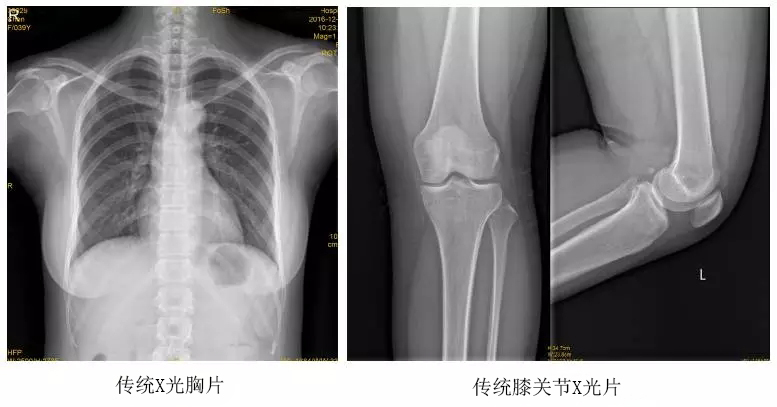

以某院所攝X光片為例,對比傳統(tǒng)攝片與全身拼接功能的區(qū)別:

傳統(tǒng)X光片只能觀察每個部位的局部情況,無法在統(tǒng)一體上進行連續(xù)、全面的觀察,全脊柱及下肢全長片則能直觀的看到整體形變。通過DR全身拼接功能實現(xiàn)的完整成像,為診治脊柱及下肢畸形提供了完美的臨床影像依據(jù),對臨床診斷、術前手術方案的制定和術后療效的評估等臨床應用具有十分重要的意義,有效滿足了此類疾病臨床診斷和治療的要求。